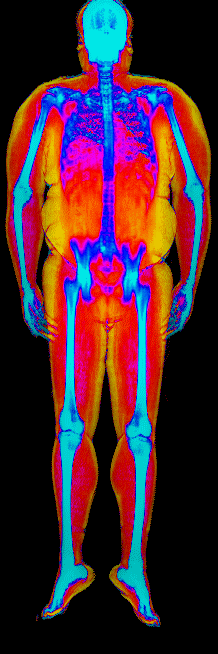

Each colorized scan shows the distribution of fat tissue (shown in warmer colors) and lean tissue (cooler colors) throughout the body. Compare your own DEXA scan to others in your range, or see what different body fat levels actually look like on a scan.

Male DEXA Scans by Body Fat %

30 to 35% body fat

35 to 40% body fat

40 to 45% body fat